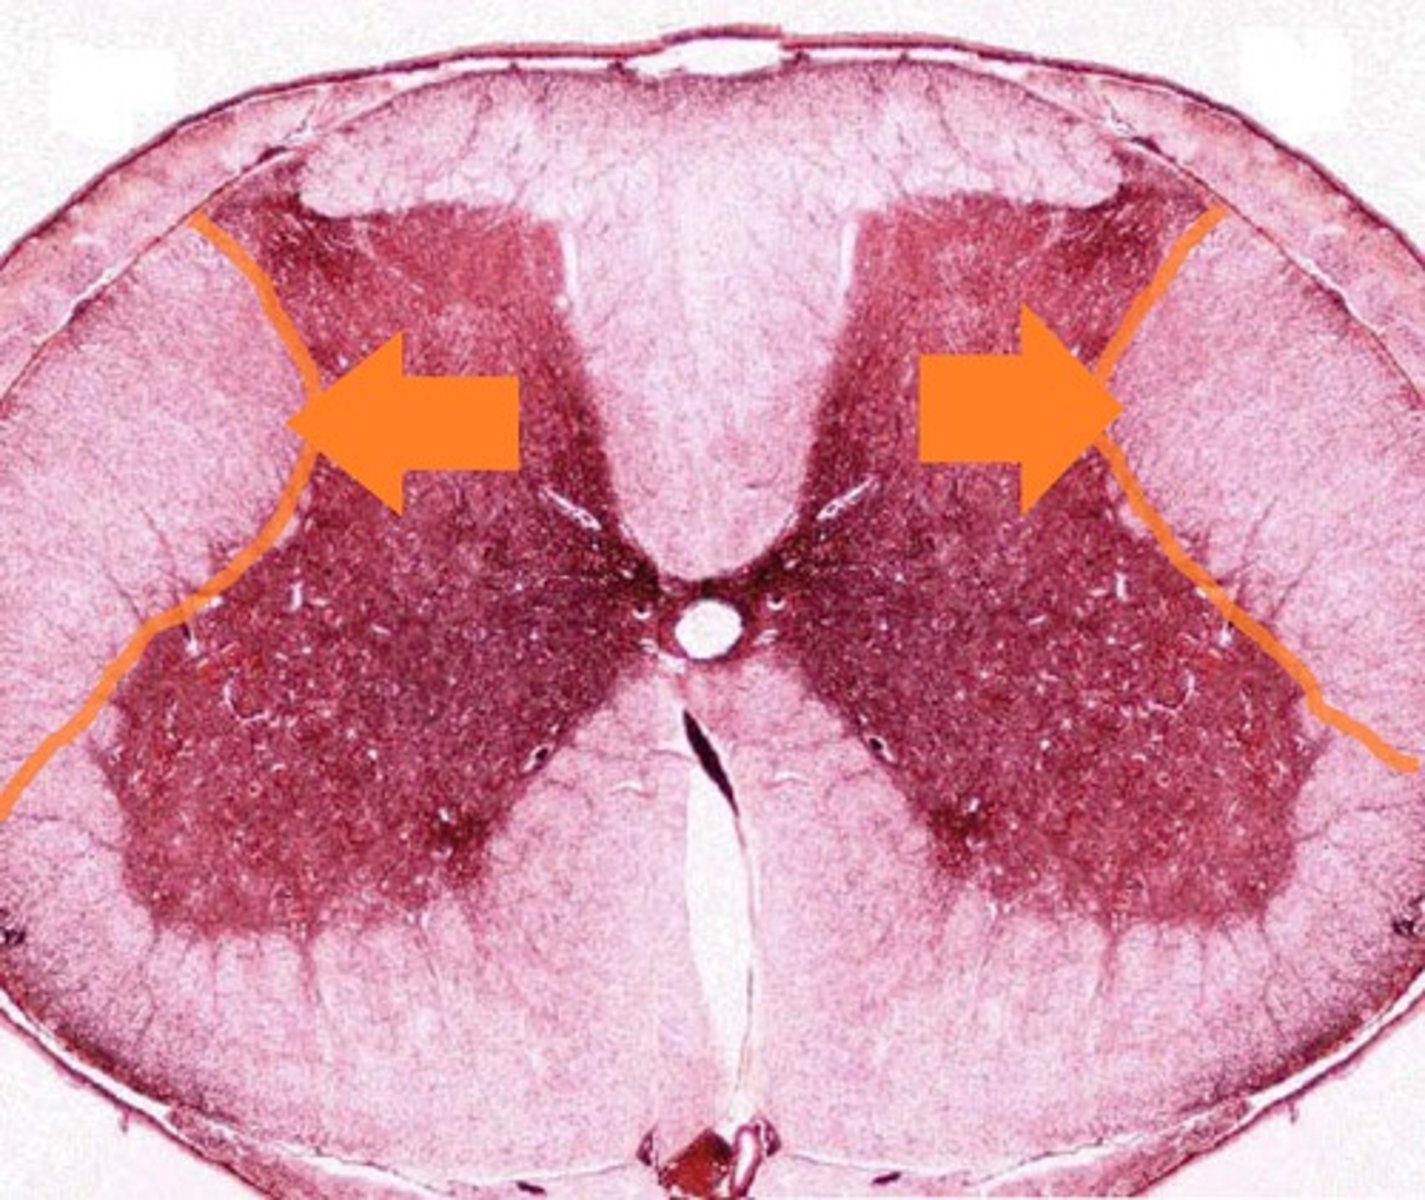

Gray Matter

1

Posterior Horn

2

Anterior Horn

3

Lateral Horn

4

Gray Commissure

6

Central Canal

5

White Matter

7

Posterior funiculus

8

Anterior Funiculus

9

Lateral Funiculus

10